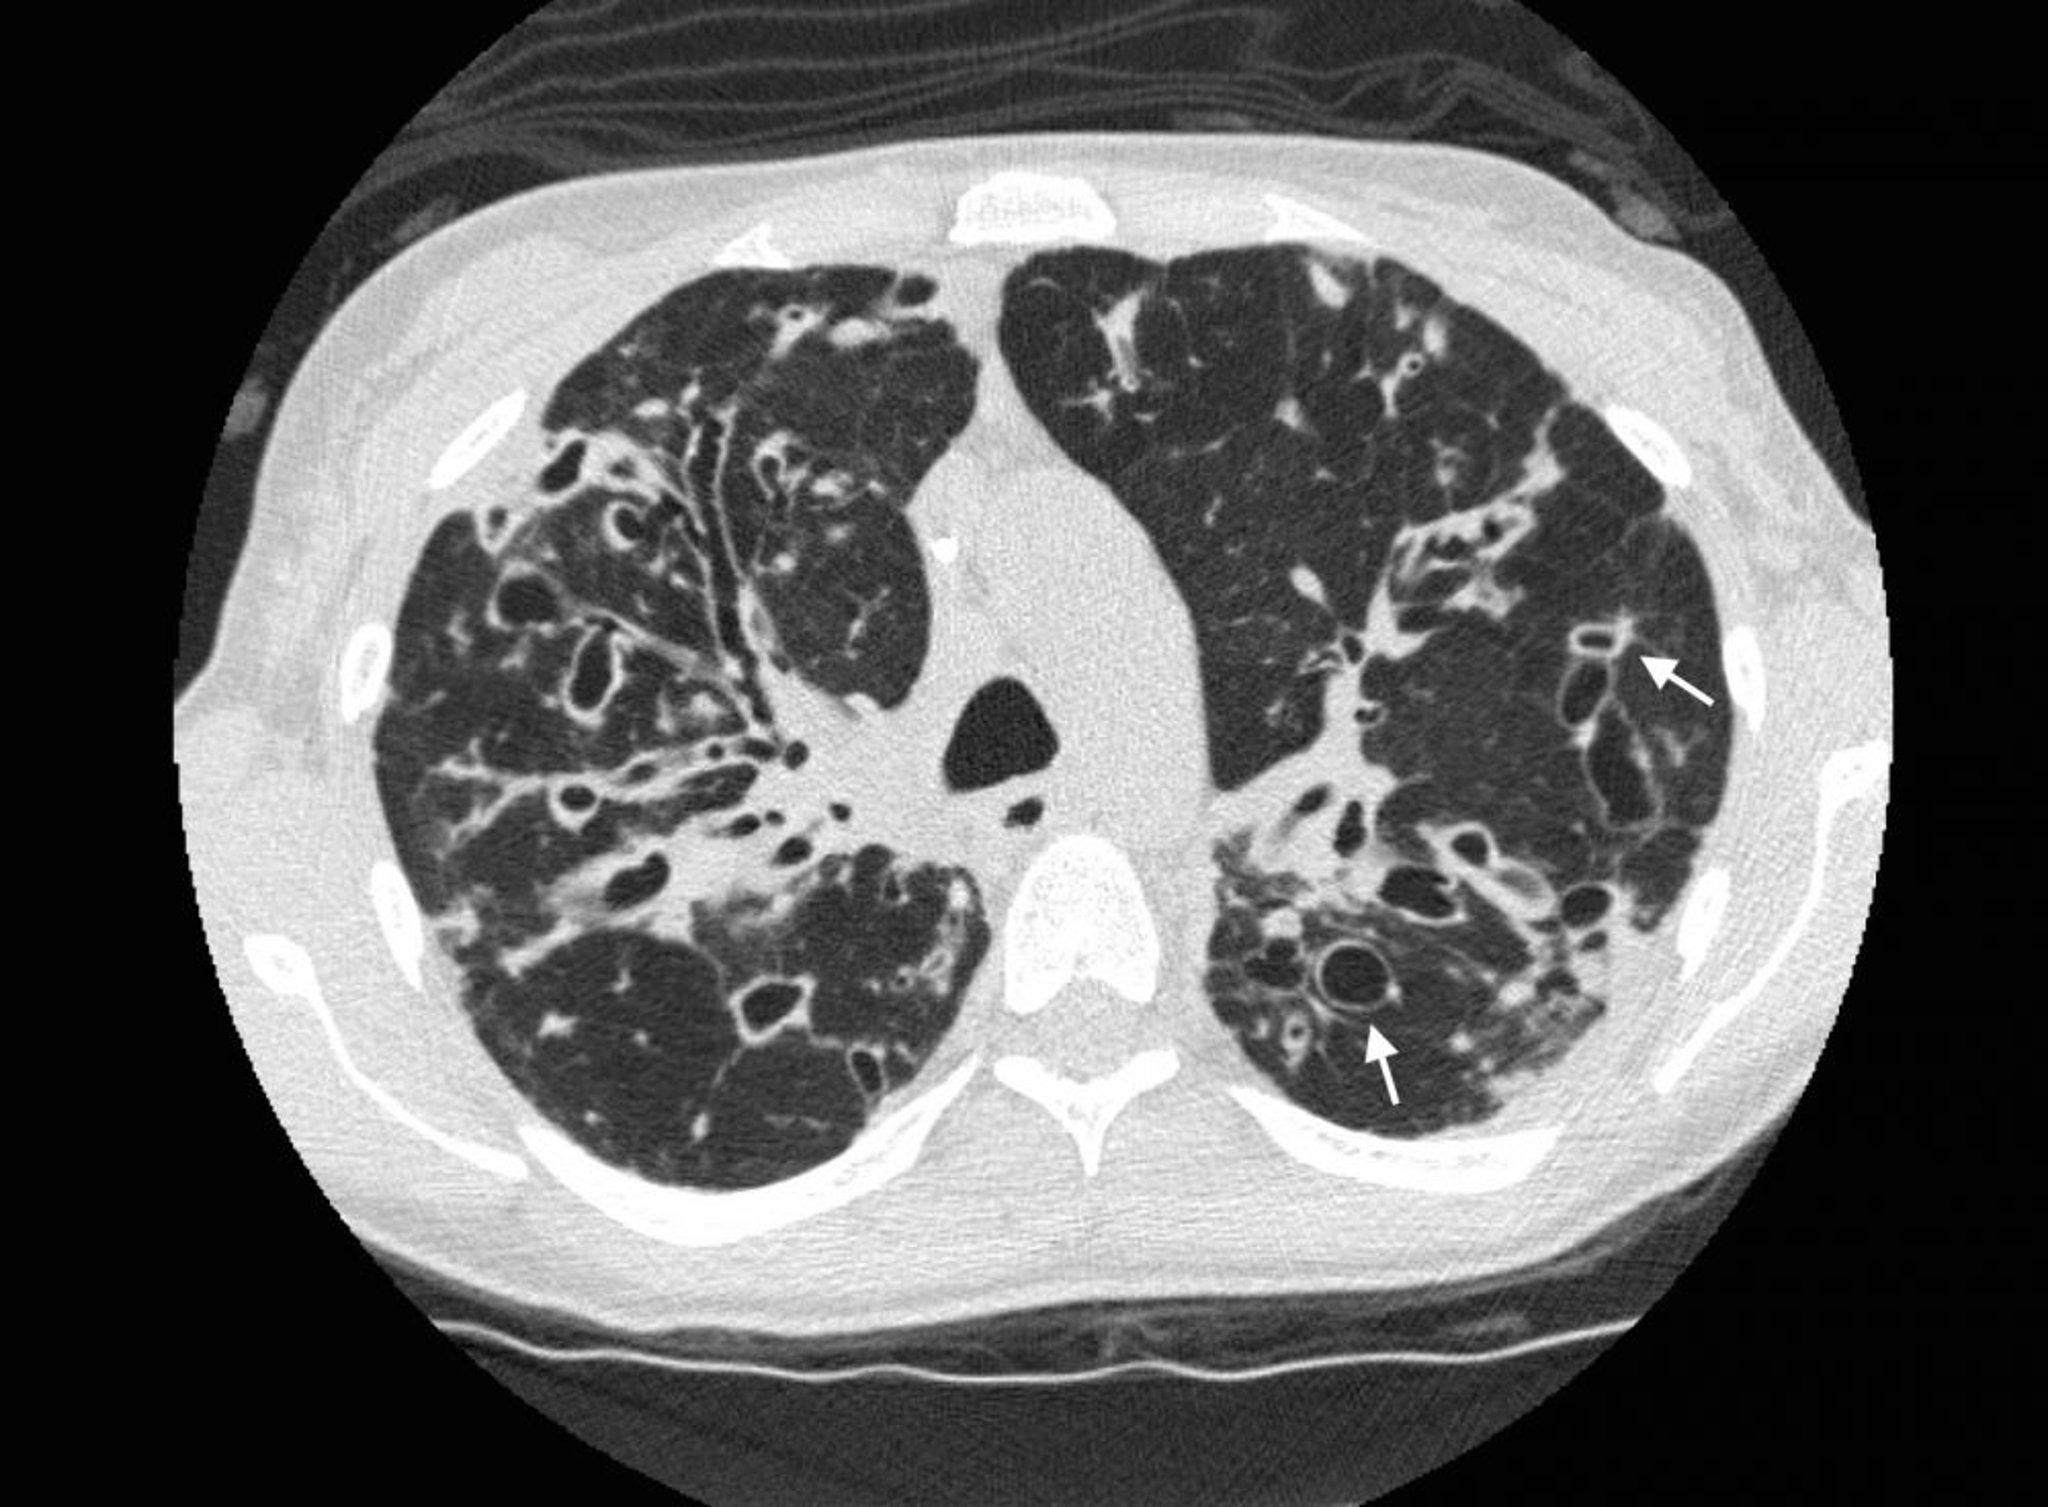

Бронхоэктатическая болезнь (компьютерная томография)

КТ грудной клетки у пациента с муковисцидозом показывает тяжелые бронхоэктазы в верхних зонах легких с расширением дыхательных путей и кистозными изменениями. Стрелки указывают на симптом перстня, то место, где расширенные дыхательные пути (кольцо) примыкают к меньшей по размеру артерии (верхняя часть кольца). Как правило, размер дыхательных путей совпадает или не превышает размер прилежащих артерий.

Photo courtesy of Başak Çoruh, MD.